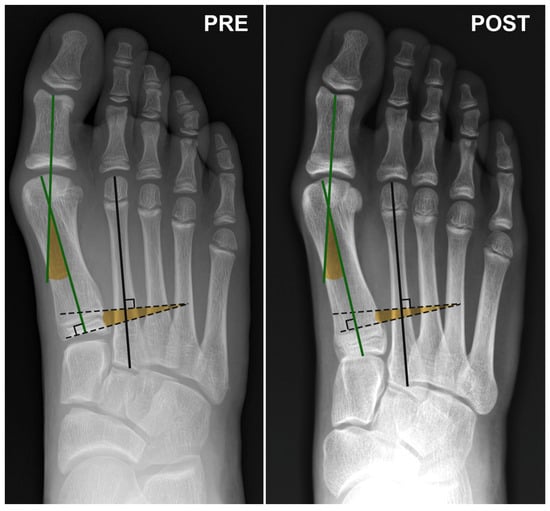

Regarding hindfoot-related angles, Meary, Costa Bartani, and Calcaneal Pitch showed an improvement but no significant difference was observed between the preoperative and postoperative measurements (Table 1 and Table 2, Figure 1 and Figure 2).

Figure 1. Dorsoplantar X-ray view of the foot of an 11-year-old female patient at the time of surgery and at the 6-month postoperative follow-up. Angle subtended by the green lines: Hallux Valgus Angle (HVA); Angle subtended by the black dashed lines: InterMetatarsal Angle (IMA).